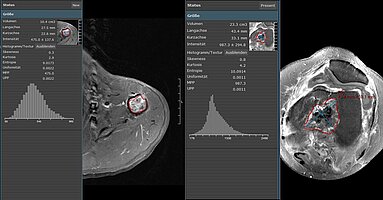

University Hospital Tübingen: Study shows prediction power of clinical and CT imaging biomarkers

A recent retrospective study [1] conducted by researchers at University Hospital Tuebingen focused on identifying imaging and clinical predictors of overall survival and treatment response in…